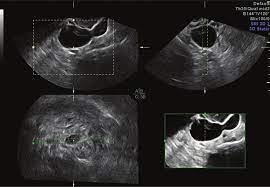

Gynecological ultrasound, also known as pelvic or transvaginal ultrasound, is a non-invasive imaging technique that uses high-frequency sound waves to create detailed images of the female reproductive organs, including the uterus, ovaries, fallopian tubes, and surrounding pelvic structures. Furthermore, gynec ultrasound allows early detection of abnormalities such as ovarian cysts, fibroids, endometriosis, polycystic ovarian disease (PCOD), and uterine growths. Therefore, it is a crucial diagnostic procedure for women experiencing irregular periods, pelvic pain, infertility, or other reproductive concerns.

• Pelvic Examination and Imaging: Next, a transabdominal or transvaginal ultrasound is performed to visualize reproductive organs in detail.

• Imaging Process: Depending on the clinical need, either transabdominal or transvaginal ultrasound is performed to capture detailed images.

• Real-Time Analysis: High-resolution imaging allows immediate detection of abnormalities such as cysts, fibroids, or endometrial changes.